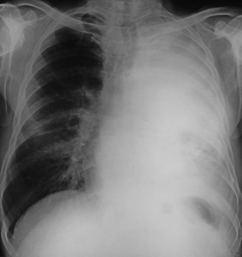

Rx toracică, incidență P-A

DESCRIERE:

DX: atelectazie prin NBP central endobronșic (pe bronhia principală stg)

DD: pleurezie masivă → caracter expansiv

la niv. întregului hemitorace stg → opacitate extinsă, nesistematizată, de intensitate mare, omogenă

caracter retractil → tracționează traheea și mediastinul de partea afectată

fără bronhogramă aerică

duce la micșorarea spațiilor intercostale

la niv. hemitoracelui controlateral → hipertransparență compensatorie (emfizem)